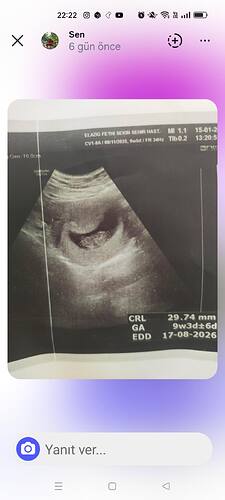

Şimdi sordum çok net değil ama kız gibi dedi bu çok öncesinin fotoğrafı 12 haftalıkken çekilmişti en son olan fotoğraf doktorun kendisinde bakalm bu sefer daha net söyler inşAllah

Kız gibi dedi Nuba göre